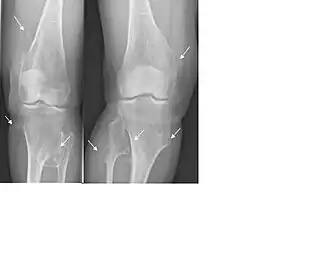

Karakteristiek zijn de (vele) in principe goedaardige bottumoren (exostosen; osteochondromen) die voorzien zijn van kraakbeenkap en waarbij de mergholte verbinding heeft met die van het betreffende bot. Ze zijn vrijwel altijd gelokaliseerd rondom een gewricht en worden bij HME in tegenstelling tot bij het solitaire osteochondroom niet beschreven in de schedel of het aangezicht. Het osteochondroom kan gesteeld of breedbasisch zijn en heeft altijd een groeirichting van het gewricht af. De exostosen ontstaan vaak al op zeer jonge leeftijd (peuter- of kleuterleeftijd) en groeien vooral tijdens de groeileeftijd erg hard. Ze veroorzaken regelmatig vergroeiingen, groeistoornissen, bewegingsproblemen en pijn. Met name bij lokalisaties rondom de knie wordt een pijnlijke bursa onder de aanhechting van de hamstrings pes anserinus op het scheenbeen beschreven. Pijnklachten als gevolg van tractie op de zenuwen of pezen wordt ook frequent gezien.[2] Lokalisaties van osteochondromen in de pols kunnen ernstige deformiteiten (verkorting van de ulna en bowing van de radius) veroorzaken (39-60%). In 10-50 % van de patiënten wordt een beenlengteverschil beschreven en in 8-33% varus-valgus angulatie van de knie (O- of X-benen).[2] Grote gesteelde osteochondromen, met name in de onderste extremiteit, lopen de kans af te breken bij lichamelijke activiteiten of ongevallen. Dit wordt in ongeveer 5% van de gevallen beschreven. Ten slotte wordt soms een afwijkende wondgenezing bij HME-patiënten beschreven.

HME wordt vaak vastgesteld aan de hand van röntgenfoto's. In het algemeen wordt aangenomen dat men kan spreken van een HME-MO als er meer dan 2 exostosen/osteochondromen bestaan. Aanvullend onderzoek kan nodig zijn in de vorm van een CT-scan, een nucleaire bot-scan of MRI-scan om zo nog onbekende lokalisaties (bv achter de scapula of in het bekken/wervelkolom) van osteochondromen te diagnosticeren. Een MRI scan van de exostose zelf kan worden gebruikt om de dikte van de kraakbeenkap bij volwassen patiënten te meten. Een kraakbeenkap dikker van 1 cm kan een aanwijzing zijn voor maligne degeneratie. Verder worden op een MRI-scan de aanwezigheid van; een weke delenuitbereiding, in het bijzonder als er verkalkingen in de weke delen bestaan, een onregelmatig oppervlak of een 'septal and ring enhancement pattern' van de kraakbeenkap en cortexdestrucie gezien als kwaadaardige radiologische kenmerken. Na de puberteit (na het sluiten van de groeischijven)ontstaan er geen nieuwe exostosen meer en behoren bestaande exostosen niet te groeien. Is er na de puberteit toch sprake van pijn of groei is het verstandig extra onderzoek in de vorm van een MRI-scan te verrichten. Veelal werd een botscan gebruikt om een kwaadarige ontaarding van een osteochondroom te beoordelen. Deze kan alleen niet differentiëren tussen een actieve kraakbeenkap met enchondrale kraakbeen afzetting en kwaadaardige ontaarding. Met het intreden van het gebruik van de MRI-scan is de beoordeling van de kraakbeenkap dan ook sterk verbeterd.